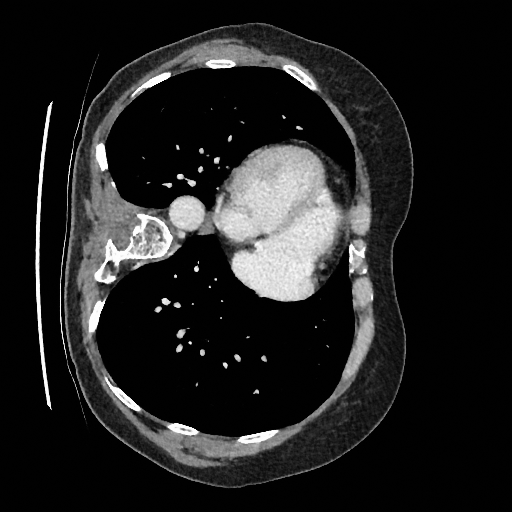

Training a continuous-time score network on Abdomen CT

Hardware: 8 NVIDIA RTX A5000 (24 GB of RAM each)

Sampling results

Original

Perturbed

Samples

Sampled